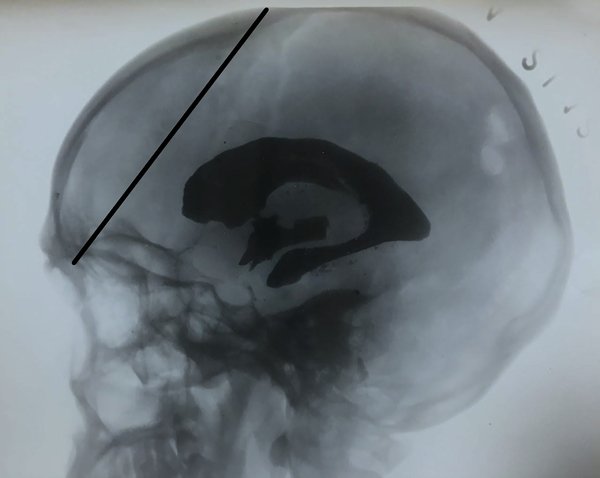

Debe señalarse aquí que la trayectoria de la aguja hacia la sutura coronal,8 siguiendo a Freeman, no tuvo en cuenta que la leucotomía transorbitaria tenía también como objetivo evitar el ingreso al sistema ventricular. Basta observar una ventriculografía (Figura 5) para percibir el error. Es así que salvo la presencia de grandes dilataciones ventriculares convendrá inclinar la aguja hacia la sutura sagital dos a tres traveses de dedo posteriores a la sutura coronal, más posterior cuanto menos dilatación ventricular exista. Entonces, una vez transpuesto con una ligera presión el techo orbitario, se avanza progresivamente la aguja, usualmente unos 3 centímetros o más, hasta observar la salida de LCR.

Figura 5: En esta ventriculografía positiva, iodoventriculografía, es clara la relación entre los cuernos frontales y las referencias óseas. Intentar una trayectoria hacia la sutura coronal puede no alcanzar un sistema ventricular moderadamente dilatado. Orientar la aguja hacia la sutura sagital algunos centímetros posteriores al bregma posibilitará el acceso a mano alzada del cuerno frontal. Como detalle se aprecian los orificios parietales de punción. Imagen ventriculográfica (histórica) cortesía del Dr. Matías Baldoncini.